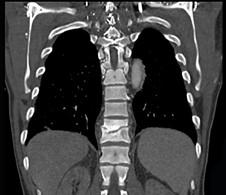

问题 男,36岁,腰背部疼痛,局部软组织肿胀,夜间加重,背部有过外伤史,有过结合图像,最可能的诊断是 ( )

选项 A、强直性脊柱炎 B、结核性骨髓炎 C、硬化型骨肉瘤 D、慢性骨髓炎 E、骨样骨瘤

答案 D